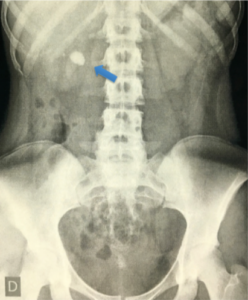

- Composição e Radiopacidade (Raio-X):

- Radiopacos (Visíveis): Oxalato de Cálcio (di-hidratado e mono-hidratado) e Fosfato de Cálcio.

- Pouco Radiopacos: Magnésio-amônio-fosfato (Estruvita – associados à infecção) e Cistina.

- Radiotransparentes (Invisíveis no RX): Ácido úrico e Urato de amônio.

- Padrão-Ouro:Tomografia Computadorizada (TC) de Abdome e Pelve SEM contraste.

- Ela vê todos os tipos de cálculos (inclusive ácido úrico), define o tamanho exato, a densidade (Hounsfield Units) e a distância pele-cálculo (útil para litotripsia). A única exceção importante são os cálculos de Indinavir (medicamento antirretroviral), que permanecem radiotransparentes mesmo na TC, exigindo confirmação por urografia excretora ou endoscopia.

💡 DICA CLÍNICA: Se o paciente tem cólica típica, mas o RX simples é normal, suspeite de cálculo de ácido úrico ou leve em conta que o cálculo pode ser pequeno ou estar sobreposto a ossos/gases. A Tomografia (TC), que é o padrão ouro, resolve essa dúvida.